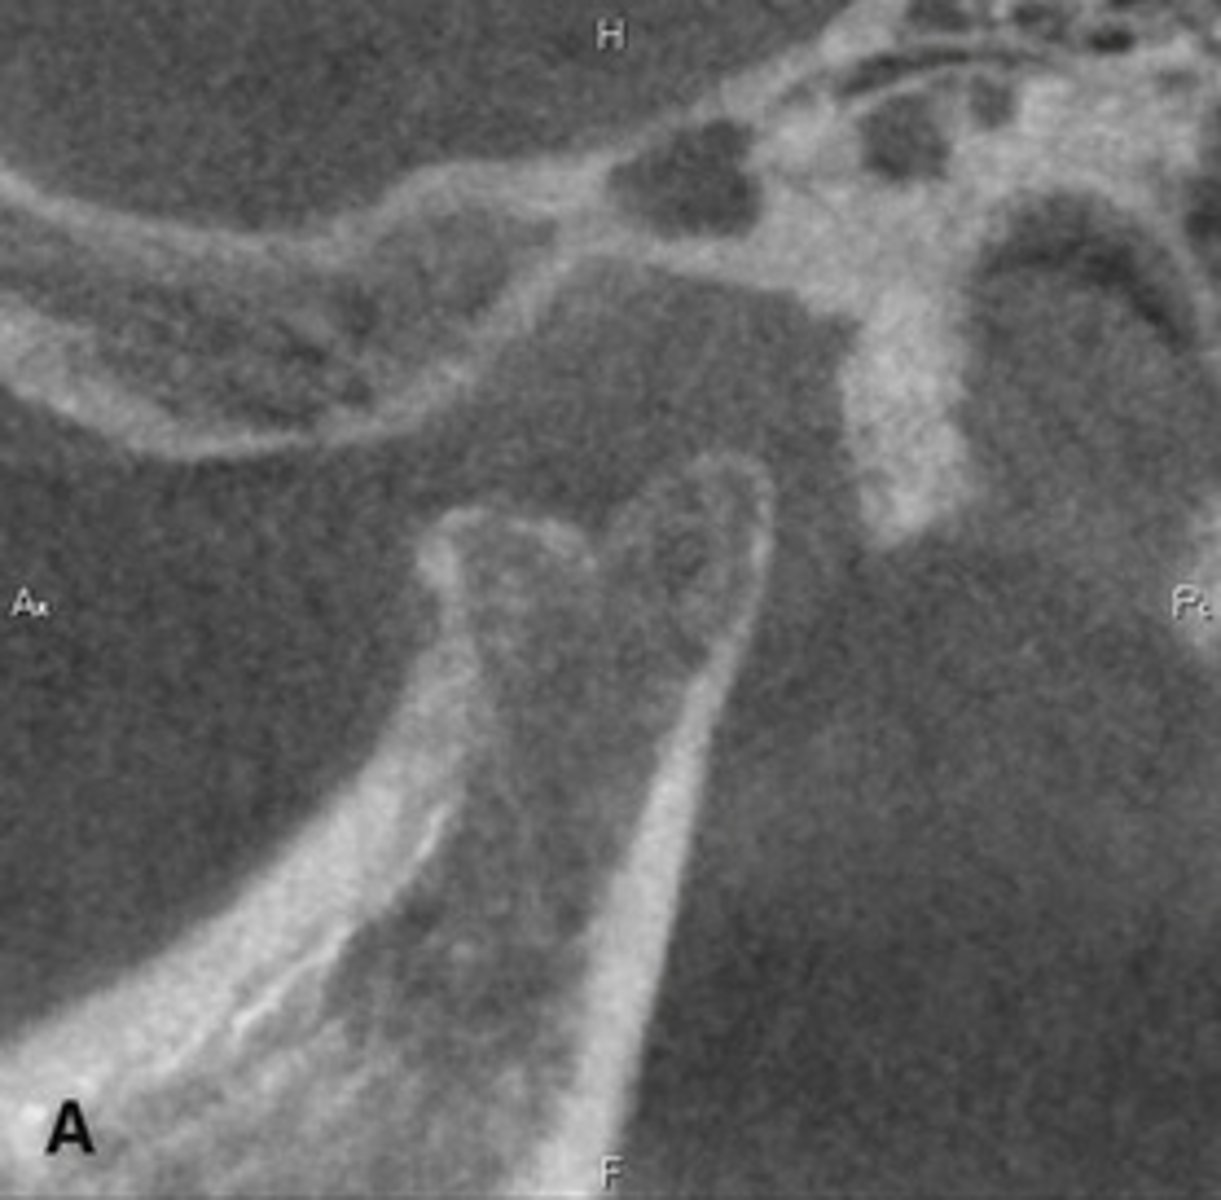

The bottom radiographs depict a developing 7year-old child.

1. The cortication of all the articulating surfaces are thin.

2. The mandibular fossa is shallow

3. The articular eminence is short

The top images are being compared to the bottom images, which patient is younger and what are all the ways to know this.